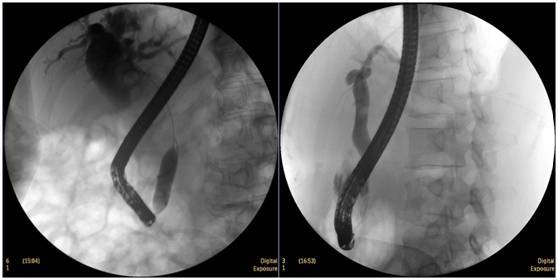

食管惡性腫瘤

食管癌并狹窄內(nèi)鏡下擴張支架植入術(shù),支架在脊柱背景下依然能清晰顯示。